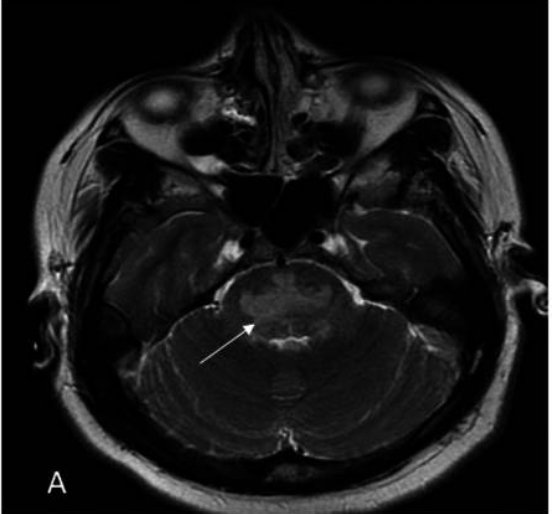

典型核磁:三叉戟征